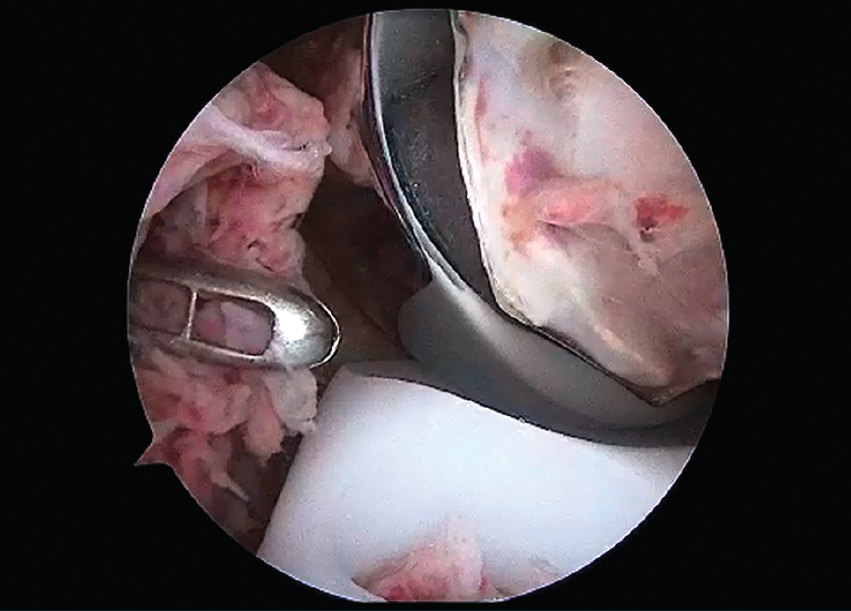

La cirugía artroscópica permite diagnosticar y tratar problemas asociados a la cirugía protésica de rodilla como artrofibrosis o dolor sin causa evidente(1). Es una técnica demandante porque puede lesionar los componentes protésicos y es dificultosa por el efecto espejo del metal. En este caso, se aprecia la toma de biopsia sinovial en prótesis total con episodios repetidos de hidrartrosis inespecíficos.